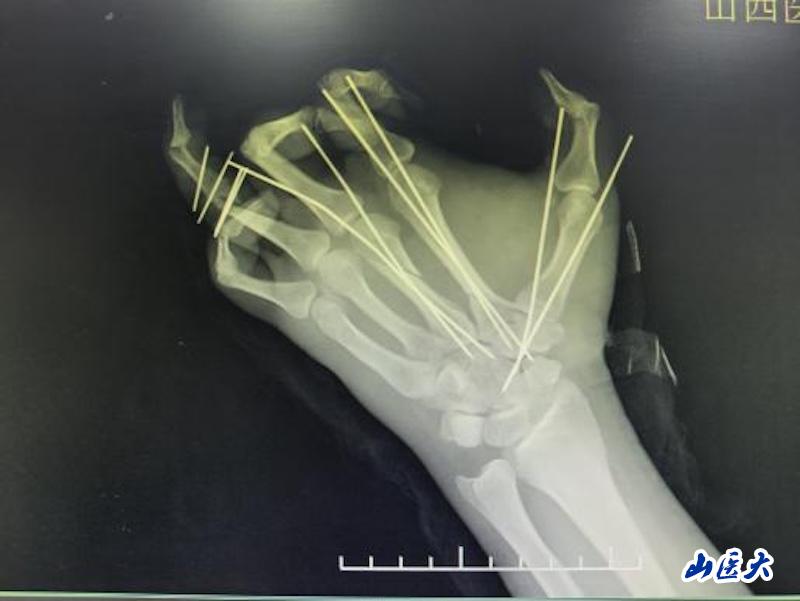

无影灯下,李广荣、武永辉、房格等医师全神贯注。首先彻底清创,标记重要的神经和血管;接着固定掌骨,建立稳定的骨架;然后开始最关键的环节——血管吻合。然后是神经吻合,这关系到手掌未来的感觉和功能恢复。最后是肌腱缝合,为手部运动功能打下基础。6个小时,在高度集中和精细操作中转瞬即逝。当最后一针缝合完成,小张离断的手掌重新回到了他的腕部,血运良好。

手掌血管直径仅0.3-0.5毫米,不足普通针孔大小;医生需要在手术显微镜下,使用比头发丝更细的11-0缝线,将断裂的血管重新吻合。手掌包含27块骨骼、多条肌腱、复杂的神经血管网络;再植手术必须依次完成骨骼固定、伸屈肌腱修复、神经对接、动脉静脉吻合等多个环节,每个环节都要求极高的精度和恰当的顺序安排。